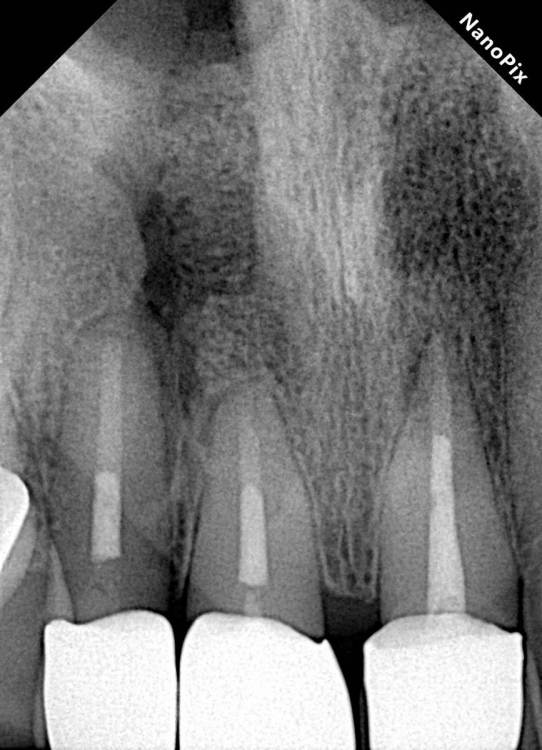

Огромная «киста» во фронте

Кортикалки не было, во второе посещение в каналах удалось добиться сухости

закрыл триоксидеКнтом на случай если понадобится апикалка

Где то через год после консервативного лечения

дальше пациент пошла на апикалку, но попала к обычному хирургу, который просто »почикал» корень бором… слегка))

дальше были осмотры каждый год и вот спустя 4,5 лет результат

На КЛКТ прослеживается ороназальное  сообщение (его и на прицелках видно). Пациента ничего не беспокоит, функция и эстетика восстановлены